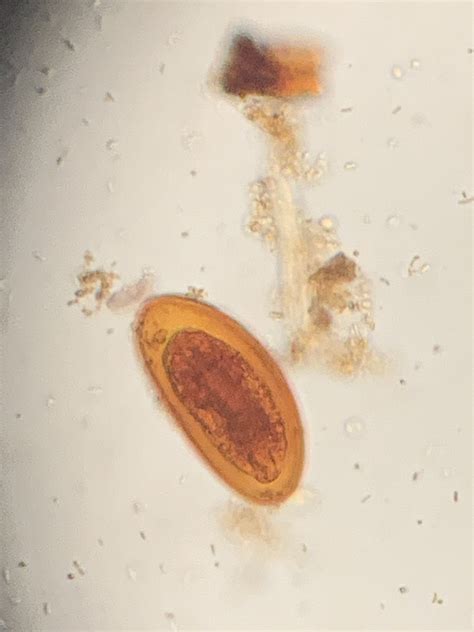

Once the sample is examined under a microscope, the presence of pinworm eggs can be confirmed. If pinworm eggs are found on the tape, it indicates a pinworm infection. The healthcare provider will then recommend appropriate treatment options, which typically involve oral medication to eliminate the worms.